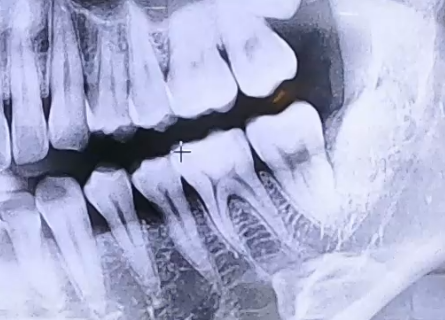

매복 사랑니 치료 사례

AFTER

사랑니로 인한 극심한 통증으로 내원해 주신 환자분입니다.

검사를 진행해 보니 매복 사랑니를 갖고 계셨고, 이 사랑니 아래쪽으로

잇몸에 염증이 생겨 잇몸뼈들이 녹아내리고 있었는데요.

해당 부위의 잇몸이 전반적으로 약해져 있었기 때문에

사랑니 발치 후 그 앞쪽 어금니들의 상태도 주의깊게 살펴야 했습니다.

다행히도 어금니는 많이 흔들리지는 않는 상황이었으므로 사랑니를 발치하고,

약해진 잇몸뼈가 회복될 수 있도록 한 뒤 뼈의 높이를 올리고 보강해 주기 위한

뼈이식 치료를 함께 진행해 드렸습니다.